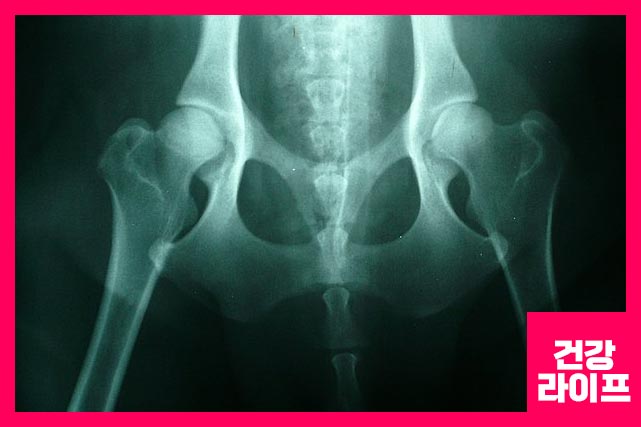

걸을 때, 앉아 있을 때, 고관절 통증 증상 때문에 고통을 겪고 계시지 않나요? 그렇다면 고관절 손상을 의심해 봐야 합니다. 고관절은 운동 범위가 큰 관절입니다. 골반과 넓적 다리뼈와 연결되었으며, 근육과 힘줄로 쌓여 있어서 하중을 견디고 분산하는 역할을 합니다.

고관절 통증 원인 10가지

원인은 다음의 10가지가 일반적입니다. 퇴행성, 비만, 출산, 자세 등 고관절에 충격 또는 손상을 가하는 경우와, 음주 습관, 흡연 습관 등 혈액순환에 악영향을 미칠 때 생기게 됩니다.